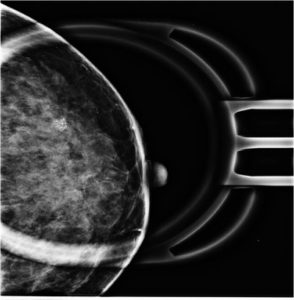

59 Yr old female, referred from outside for suspicious microcalcifications in left breast.